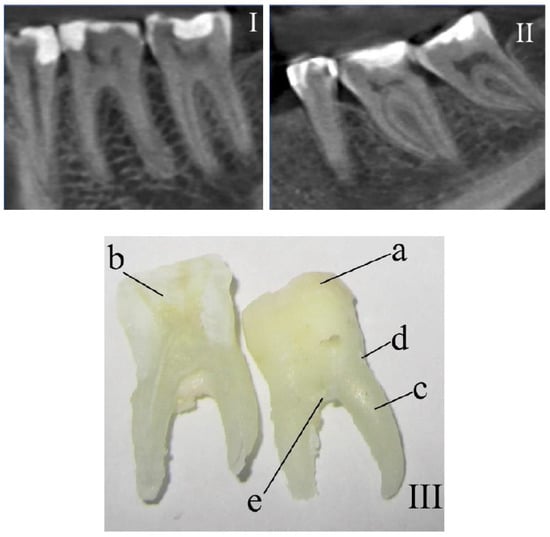

The surfaces of teeth in 5 different areas were studied: enamel (a), dentin (b), in longitudinal slices), cementum (c), and dental calculus localized in the outer part of the teeth. The degree of intensity of the surface formation of the studied teeth corresponded to distinct under-gum (e) and above-gum (d) calculus [17].

Three spectra were investigated (with subsequent averaging) in every studied area at 3–5 different points of the surface of every tissue of each tooth. Samples were divided into 2 main groups: the control group (Figure 1I) and the group with periodontitis (Figure 1II).

Figure 1. The fragments of teeth following computed tomography that were (I) healthy and (II) diagnosed with periodontitis. (III) Photo of a tooth with the researched areas indicated: a—enamel, b—dentin, c—cementum, d—above-gum dental calculus, and e—under-gum dental calculus.